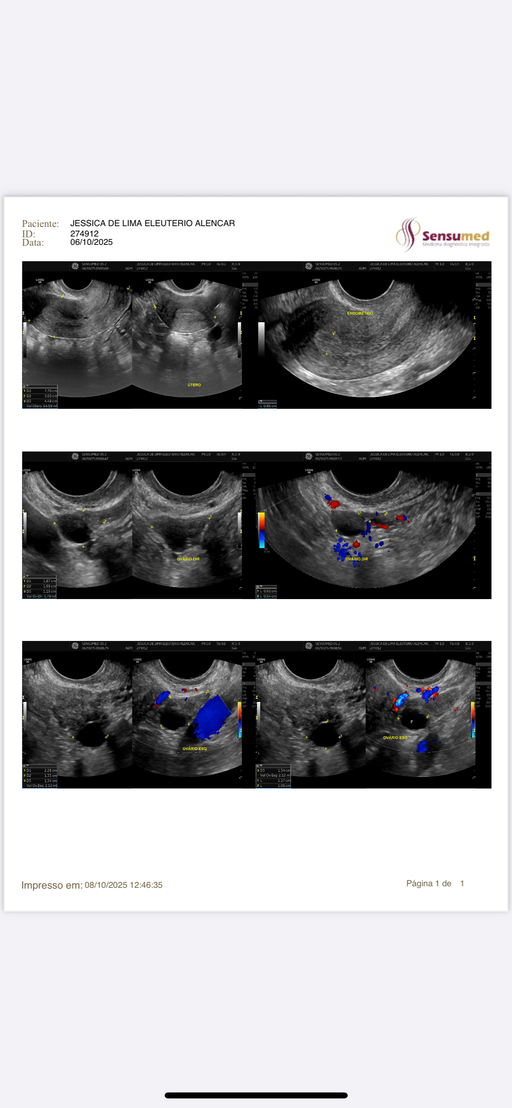

JESSICA DE LIMA ELEUTÉRIO ALENCAR

Oct 8, 2025

Resultado de US